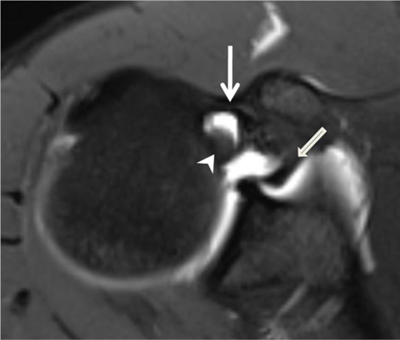

Figure 24

Pulley system. Axial fat-saturated T1-weighted MR arthrographic section at the level of the bicipital groove shows the biceps pulley (large arrow), formed by the fusion of the coracohumeral ligament, the superior glenohumeral ligament (thin arrow) and the transverse humeral ligament. The long head of the biceps tendon is pointed out by an arrowhead.